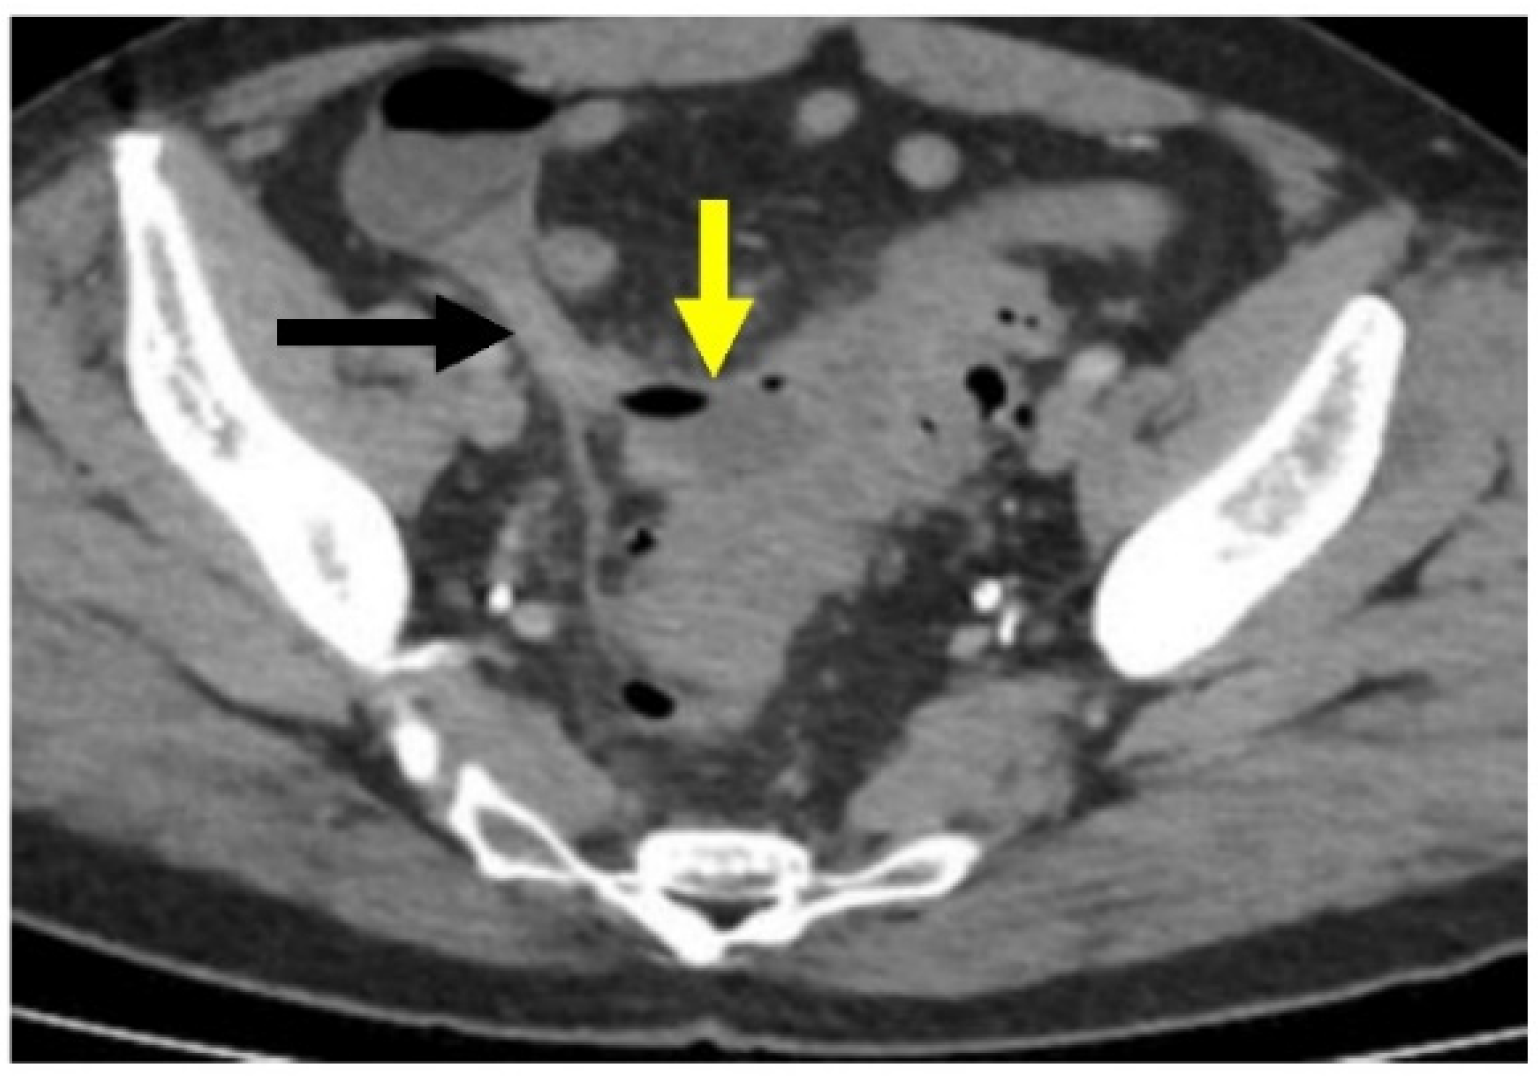

Figure 5.

Acute sigmoid diverticulitis complicated by peridiverticular abscess. Axial CT with IV contrast through the pelvis. There is a rim-enhancing collection of fluid and air along the medial wall of the sigmoid colon (yellow arrow), compatible with abscess. This also abuts the appendix (black arrow), with possible fistulous communication.

CT scanning can show complicated disease as a peridiverticular mesenteric inflammatory reaction (Hinchey Ib) or microperforation with adjacent extraluminal air (Figure 6). Contrast is also helpful to evaluate for potential abscess (Hinchey Ia or II), where rim-enhancement will be seen (Figure 5).

Acute complicated diverticulitis has been further subclassified in the surgical literature using the Hinchey Classification. Developed by Hinchey et al. in 1978 and later modified with the widespread usage of CT scanning (see Table 2), the Hinchey classification divides acute complicated diverticulitis into four categories based on whether the perforation is localized or not [28,29,30]. Classes I and II, a pericolic abscess or phlegmon (Figure 5) and distant pelvic intra-abdominal or retroperitoneal abscess, respectively, do not cause peritonitis or hemodynamic changes. Hinchey classes III and IV, generalized purulent and feculent peritonitis, respectively, often do. The modified Hinchey classification is a helpful adjunct to determine management, with purulent and fecal peritonitis (classes III-IV) most likely to lead to surgery [4,19].